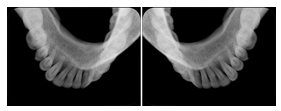

2 Occlusal Vertical Maxilla A Dental Image Layout

DL-C001A

Reference: DL-C001-U1L0

Reference: DL-C001-U2L0

00

Occlusal

18, 17, 16, 15, 14, 13, 12, 11, 13, 12, 11

01

21, 22, 23, 24, 25, 26,27, 28

2 Occlusal Vertical Mandible A Dental Image Layout

DL-C002A

Reference: DL-C002-U0L1

Reference: DL-C002A-U0L2

10

48, 48, 47, 46, 45, 44, 43, 42, 41

11

31, 32, 33, 34, 35, 36, 37, 38

2 Occlusal Horizontal Maxilla A Dental Image Layout

DL-C003A

Reference: DL-C003-U1L0

Reference: DL-C003-U2L0

18, 17, 16, 15, 14, 13, 12, 11, 13, 12, 11, 21, 22, 23, 24, 25, 26,27, 28

2 Occlusal Horizontal Mandible A Dental Image Layout

DL-C004A

Reference: DL-C004-U0L1

Reference: DL-C004-U0L2

48, 48, 47, 46, 45, 44, 43, 42, 41, 31, 32, 33, 34, 35, 36, 37, 38